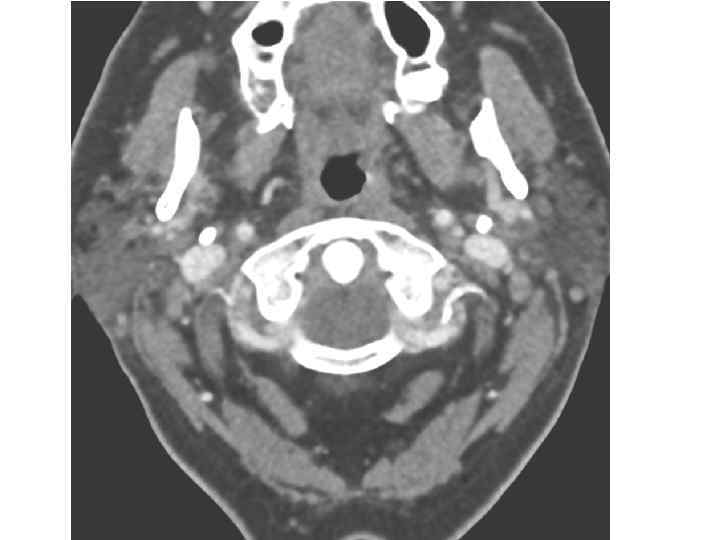

Клетчаточные пространства • межлестничное пространство, ограничено пространство передней и средней лестничными мышцами, а снизу - первым ребром (подключичная артерия и плечевое сплетение). • предлестничное пространство • спереди прикрыто грудинощитовидной и грудиноподъязычной мышцами, сзади передней лестничной мышцей (подключичная вена, надлопаточная артерия и диафрагмальный нерв).

Лестнично-позвоночный треугольник медиальный край передней лестничной мышцы и латеральная часть длинной мышцы шеи образуют угол, снизу закрытый куполом плевры ( лестничнопозвоночный треугольник), первый отдел позвоночной артерии, ее ветви, пограничный симпатический ствол.

Межфасциальные клетчаточные пространства шеи • Надгрудинное межапоневротичес кое пространство между поверхностной и глубокой пластинками собственной фасции шеи над яремной вырезкой грудины, сообщается со слепым мешком, расположенным позади грудиноключичнососцевидной мышцы.

Межфасциальные клетчаточные пространства шеи • Предвисцеральное, или предтрахеальное пространство между предтрахеальной пластинкой собственной фасции шеи и внутришейной фасцией распространяется от подъязычной кости до рукоятки грудины, где переходит в средостение.

Межфасциальные клетчаточные пространства шеи Позадивисцеральное пространство • Между внутришейной и предпозвоночной фасциями, • распространяется от основания черепа и переходит в заднее средостение грудной полости.